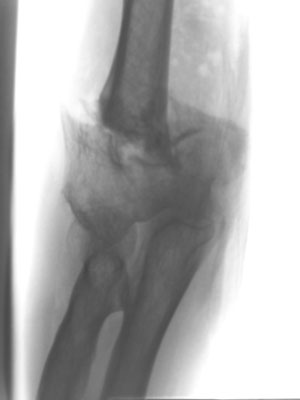

Radiusköpfchenbruch/Speichenköpfchenbruch

Einfache, sog. „Meißelbrüche“ des Speichenköpfchens können durch Minischrauben sehr stabil fixiert werden. Komplizierte Brüche müssen event. mit Miniplättchen verschraubt werden.

Bei ausgedehnter Zertrümmerung des Radiusköpfchens kann dieses mit Miniplättchen rekonstruiert werden oder sogar vollständig entfernt werden, ohne das die Funktion des Ellenbogens stark beeinträchtigt wird.

Häufiger kommt es allerdings zu zusätzlichen Bandverletzungen, insbesondere wenn der Ellenbogen luxiert war. In diesem Fall muss das Radiusköpfchen unbedingt erhalten werden, oder durch eine Radiusköpfchenprothese ersetzt werden. Durch die Wiederherstellung der knöchernen Führung wird die Stabilität des Ellenbogengelenkes wieder hergestellt. Zusätzlich wird der Bandapparat während der Operation genäht.